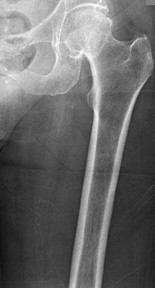

A 65-year-old male who underwent a cementless total hip arthroplasty (THA) 15 years ago presents with new-onset thigh pain. Radiographs reveal eccentric positioning of the femoral head within the acetabular shell and large retroacetabular and proximal femoral radiolucencies.

What is the primary biological mediator released by macrophages that directly stimulates osteoclastogenesis and is responsible for the observed bone loss?

Explanation

The radiograph demonstrates particle-induced osteolysis, secondary to polyethylene wear debris. When macrophages phagocytose these particles, they release pro-inflammatory cytokines, most notably TNF-a, IL-1, and IL-6. These cytokines stimulate the RANK/RANKL pathway, activating osteoclasts and leading to significant periprosthetic bone loss. IL-10 and IL-4 are anti-inflammatory cytokines, while IFN-y actually inhibits osteoclastogenesis.